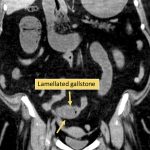

۲. وجود یه سنگ صفرا در جای نابجا

شاید پیدا کردنش آسون نباشه، چون بعضی از سنگا radiolucent هستن، ولی اگه دیده بشه، یه ساختار بیضیشکل و لایهلایهست که توی مسیر روده گیر کرده. دیدنش میتونه خیلی کمککننده باشه، بهخصوص اگه در کنار سایر علائم باشه.